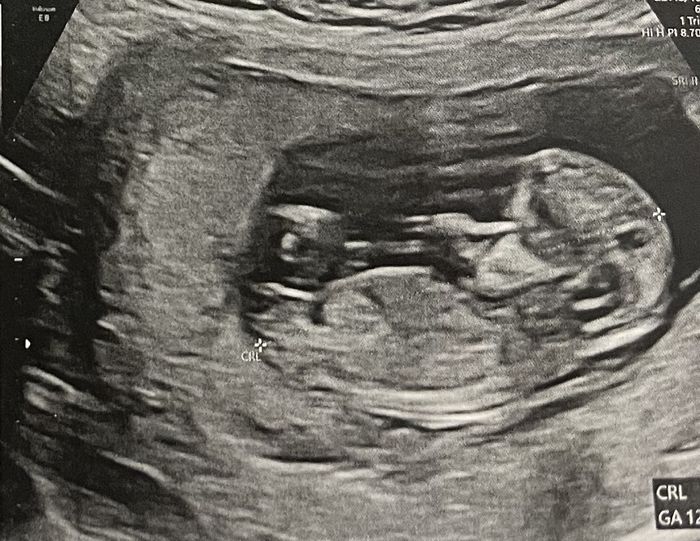

Ciao ragazze, lunedì scorso ho fatto eco genetica a 11+5 ma bebè misurava 12 settimane, ho fatto dna fetale che dovrebbe arrivare questa settimana, ma nel frattempo per ingannare il tempo e l’ansia, c’è qualcuna che se ne intende di nub theory? Io un pochino sì e quindi ho una mia idea. Sia per il tubercolo, sia per la posizione della vescica, rispetto alla spina dorsale… ma magari qualcuna qui ne capisce più di me, maschio o femmina?vi lascio un po’ di foto

cfb_2067805.jpg

cfb_2067807.jpg

cfb_2067809.jpg